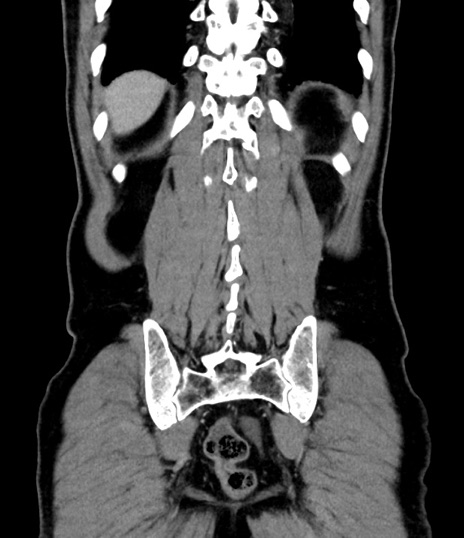

症例8(冠状断像)

【症例】 60歳代男性

【主訴】 黒色吐物

【現病歴】 4日前から嘔気自覚、2日前の朝食後にも嘔気あり、自分で手で嘔吐反射起こし嘔吐したところ血が混ざっていたため受診。

【既往歴】 5年前汎発性腹膜炎を伴う急性虫垂炎で手術、高血圧、前立腺肥大症、高脂血症

【身体所見】 腹部正中に手術癩痕あり 腹部平坦・軟圧痛なし膨満感あり

【データ】WBC 8400、CRP 4.54